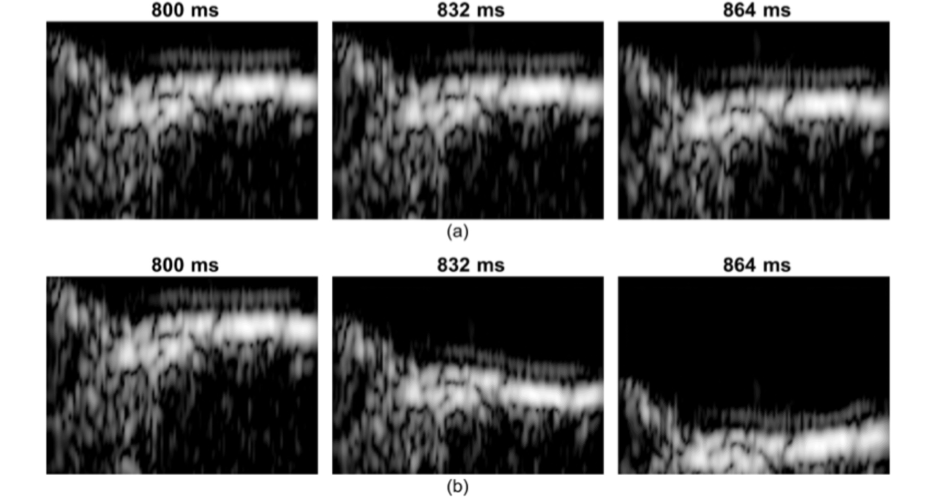

Figure Legend: Demonstration of video magnification applied to medical ultrasound imaging for one example with ultrasound (carotid). Close-up views of the distal wall are presented over time at 800, 832 and 864 ms after the beginning of acquisition. Upper row (a) is the original US images and the lower row (b) is the magnified data. Radial motion, due to the propagation of a pulse wave, is only visible on the magnified data (b).

"Video Magnification Applied in Ultrasound" IEEE Transactions on Biomedical Engineering. Vincent Perrot, Sébastien Salles, Didier Vray and Hervé Liebgott. IF = 3.577